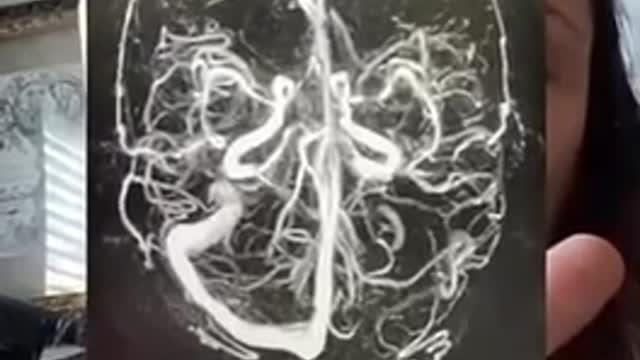

THIS IS A X-RAY OF A 👩 BRAIN AFTER THE PFIZER 💉

Cerebral venous sinus thrombosis (CVST) occurs when a blood clot forms in the brain’s venous sinuses. This prevents blood from draining out of the brain. As a result, blood cells may break and leak blood into the brain tissues, forming a hemorrhage.

This chain of events is part of a stroke that can occur in adults and children..